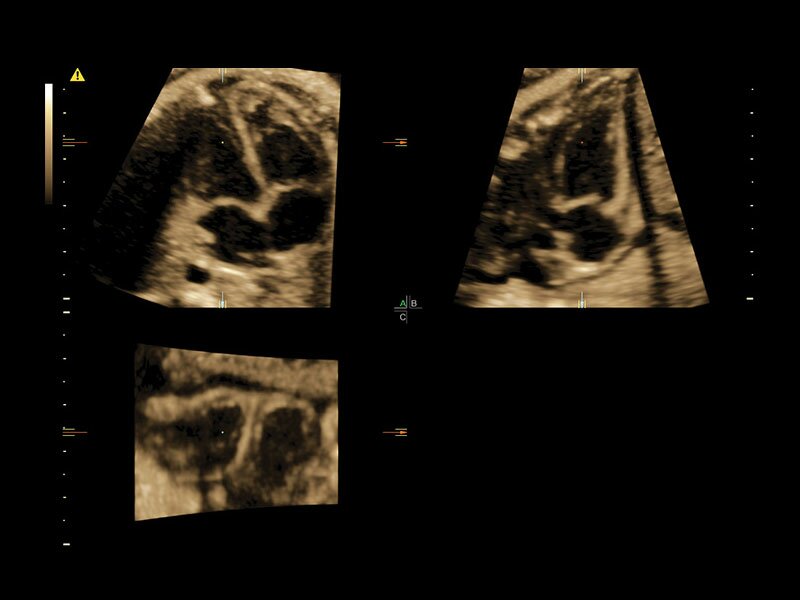

Клинические изображения

• Усовершенствованный режим объемной визуализации с контрастированием (Volume Contrast Imaging, VCI) и опция OmniView

• Повышает контрастное разрешение и улучшает визуализацию области интереса в любой плоскости сечения, даже при исследовании структур неправильной формы.

• Томографический ультразвук (TUI)

• Объемное контрастирование прямой плоскости - Basic VCI (VCI-A + VCI static)